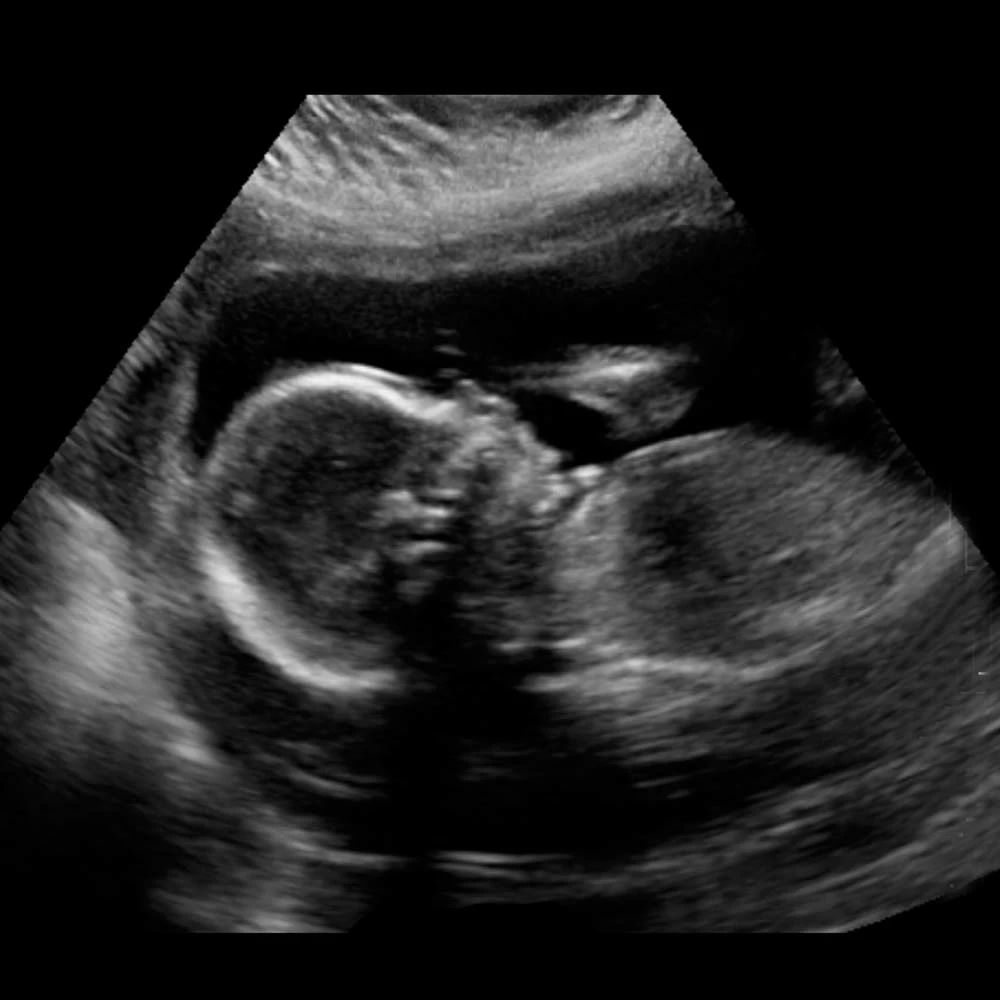

На четырнадцатой неделе при хорошем чувствительном аппарате УЗИ уже можно определить пол ребенка.